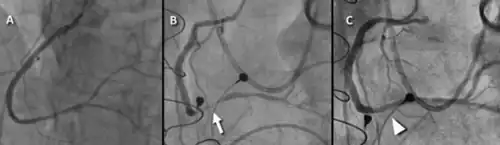

a) Preoperative angiogram b) postoperative angiogram with focal spasm at the arrow c) resolution after intracoronary nitroglycerin